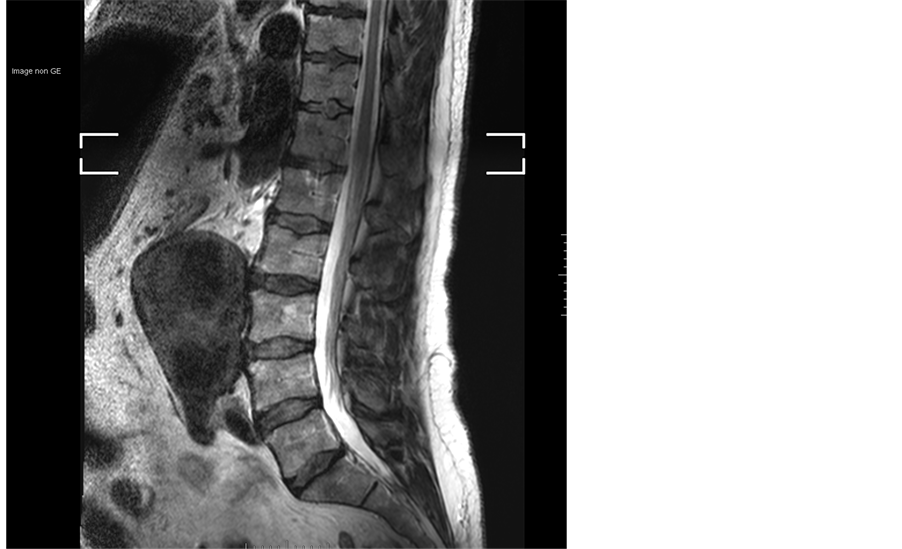

Lumbar medullar magnetic resonance imaging (MRI) was normal but showed an infrarenal AAA (Figure 1). The finding was subsequently confirmed by a contrast enhanced CT scan (Figure 2). The aneurysm was partially thrombosed with a maximal diameter of 7.5 cm with no signs for rupture.

Figure 1. Spinal MRI-sagittal T2- normal spina equida signal. Aneurysm is easily seen as a hyposignal structure.